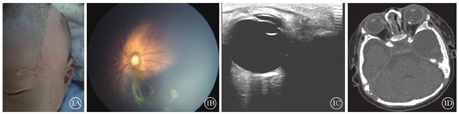

患儿男,2个月。因新生儿全身检查于2016年12月8日到吉林大学第二医院眼科就诊。患儿胎龄39周顺产。否认癫痫及全身其他器官系统病史,否认家族遗传病史。体格检查:左侧面部、颞部、耳前、眉部大片淡黄白色病变,眉部及颞部皮损呈疣状隆起,病变部位无毛发生长(图1A)。经本院皮肤科会诊,诊断为"皮脂腺痣"。双眼眼前节未见明显异常。眼底检查,左眼视盘周围约6个视盘直径大小的橘红色病灶(图1B)。彩色多普勒超声血流成像检查,左眼视神经周围强回声光带,其后可见声影(图1C)。头部CT检查,左侧眼环后部条形强密度影(图1D)。右眼眼底未见明显异常。诊断:皮脂腺痣综合征合并脉络膜骨瘤。嘱患儿家属定期复查。

研究报道,59%的皮脂腺痣综合征患者合并眼部病变,发生率仅次于神经系统病变。最常见的眼部病变为错构瘤和眼部结构缺损。错构瘤常发生于角膜、结膜,也可发生在眼睑、巩膜[7]。结构缺损常发生在眼睑、视网膜、葡萄膜。其他眼部表现包括斜视、视神经发育不良、眼睑血管瘤、巩膜纤维瘤、视盘周围脉络膜萎缩、渗出性和孔源性视网膜脱离、小眼球和皮质盲等[3,8,9]。皮脂腺痣综合征眼底改变主要表现为后极部边界不清的橘红色病灶。头部CT及眼部B型超声检查,眼环后方强密度影,与脉络膜骨瘤类似。本例患儿仅表现为皮肤的皮脂腺痣及眼部错构瘤,其他器官无明显异常。

本例患儿眼底橘红色改变,结合超声及CT检查结果,诊断为脉络膜骨瘤。脉络膜骨瘤OCT特征常表现为脉络膜内层病变、可有钙化及脱钙表现、外层视网膜结构异常等。而本例患儿OCT表现为视网膜结构清晰完整,脉络膜变薄,与脉络膜骨瘤特征不符。Traboulsi等[7]对1例皮脂腺痣综合征患者眼球行病理解剖,病变部位相应巩膜内骨或软骨组织,提示皮脂腺痣有合并巩膜错构瘤。结合本例患儿OCT检查结果,推测巩膜错构瘤可能性大,其为皮脂腺痣综合征眼部病变的一种特征性病变,而非脉络膜骨瘤。目前尚无皮脂腺痣综合征眼底表现的OCT特征描述,本文为首次报道。对于脉络膜骨瘤和巩膜错构瘤,两者鉴别要点在于:(1)脉络膜骨瘤好发于中年女性,而皮脂腺痣综合征中巩膜错构瘤好发于儿童。(2)脉络膜骨瘤较少合并其他器官系统异常,皮脂腺痣综合征常合并头颈部皮脂腺痣及中枢神经系统异常。(3)皮脂腺痣综合征眼底改变可见脉络膜大血管。(4)病理学检查发现巩膜内骨或软骨组织可确诊。患儿初诊时眼表未见异常,5年后复诊诊断为左眼上方球结膜错构瘤,提示皮脂腺痣综合征结膜错构瘤可后天发生,需注意长期观察随访。约10%~20%的皮脂腺痣患者可能为继发肿瘤,且多发生于40岁以上患者。大多数继发肿瘤为良性,约3%的恶性肿瘤,包括基底细胞癌和鳞状细胞癌[10]。